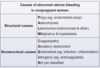

Major causes of Antepartum Hemorrhage - 3

Antepartum = right before childbirth

- Placental abruptio (PAINFUL Anterpartum hemorrhaging)

- Placental previa

- Vasa Previa

CP for Placental Abruptio - 4

Risk factors = HTN, cocaine, smoking, prior abruptio, abd trauma

- sudden PAINNNFFULLL antepartum vaginal bleeding (which can –> hypovolemic shock, [DIC-from decidual bleeding releasing tissue factor 7] and fetal demise) - (UNLESS CONCEALED = then no vag bleeding)

- Distended firm uterus

- abd AND/OR back pain

- [contractions of low intensity]

etx: HTN of maternal decidual vessels –> rupture –> premature detachment of placenta from endometrium

pregnant patient 35 WG p/w painless vaginal bleeding

Next step is (⬜ Digital Cervical Exam | TVUS) and why?

TVUS

s/f Placenta PREVIA, in which digital Cervical Exam is contraindicated since it enters endocervical canal. TVUS and speculum do NOT enter endocervical canal

_________________

Placenta Previa

Of the 3 placental demise, which is a/w painLESS antepartum vaginal bleeding?

Placenta Previa